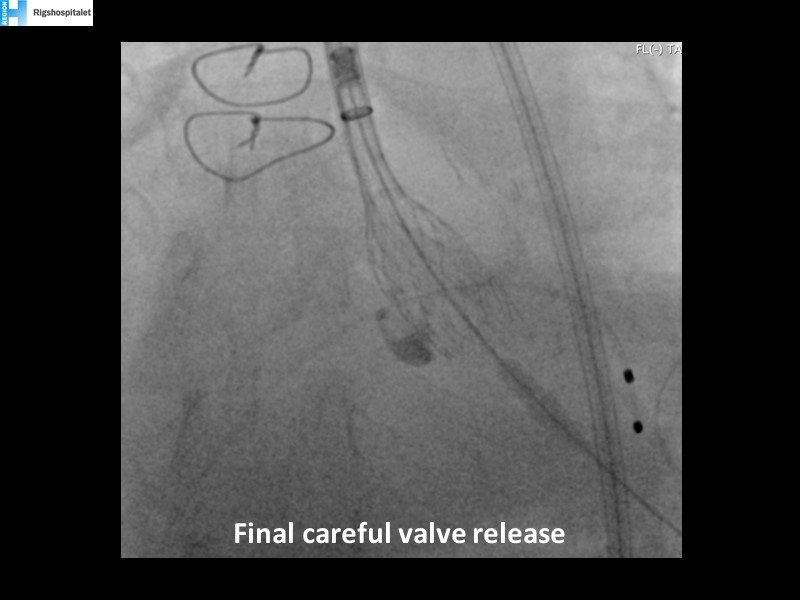

Your most challenging TAVI cases - Achieving precision and control with Evolut platform

How to deal with challenging anatomies? Find answers in this EuroPCR 2022 session with case studies to explore and learn how to achieve optimal patient outcomes with Evolut platform, uncover practical tips and techniques to achieve implant precision and control, and become familiar with technical considerations and procedural execution of TAVI.

- To become familiar with technical considerations and procedural execution of TAVI